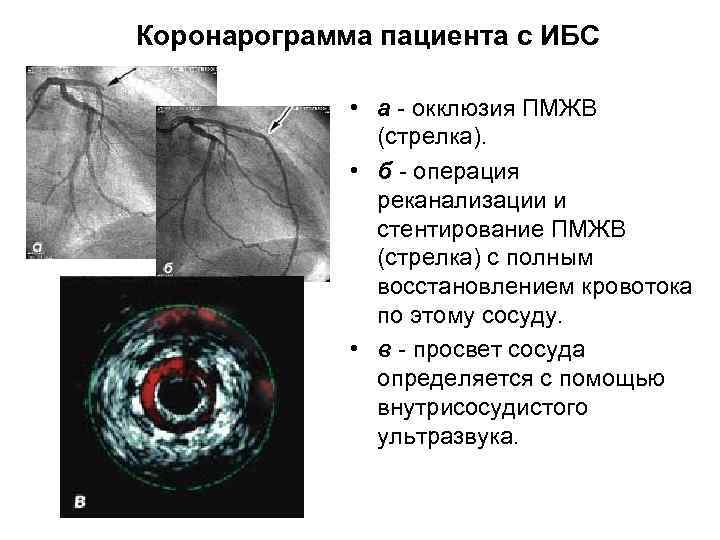

Внутрисосудистый ультразвук • исследование артерий (например, коронарных) с использованием специального внутрисосудистого датчика малого диаметра. • Инвазивный ультразвуковой метод. • Используется параллельно с коронарографией.

Внутрисосудистый ультразвук • исследование артерий (например, коронарных) с использованием специального внутрисосудистого датчика малого диаметра. • Инвазивный ультразвуковой метод. • Используется параллельно с коронарографией.

Внутрисосудистое ультразвуковое исследование (ВСУЗИ) • В то время, как ангиография остается золотым стандартом в исследовании коронарных артерий, становится все более и более важным • определение структурных изменений стенки артерии, • а не только степени сужения ее просвета.

Внутрисосудистое ультразвуковое исследование (ВСУЗИ) • В то время, как ангиография остается золотым стандартом в исследовании коронарных артерий, становится все более и более важным • определение структурных изменений стенки артерии, • а не только степени сужения ее просвета.

Коронарограмма пациента с ИБС • а - окклюзия ПМЖВ (стрелка). • б - операция реканализации и стентирование ПМЖВ (стрелка) с полным восстановлением кровотока по этому сосуду. • в - просвет сосуда определяется с помощью внутрисосудистого ультразвука.

Коронарограмма пациента с ИБС • а - окклюзия ПМЖВ (стрелка). • б - операция реканализации и стентирование ПМЖВ (стрелка) с полным восстановлением кровотока по этому сосуду. • в - просвет сосуда определяется с помощью внутрисосудистого ультразвука.